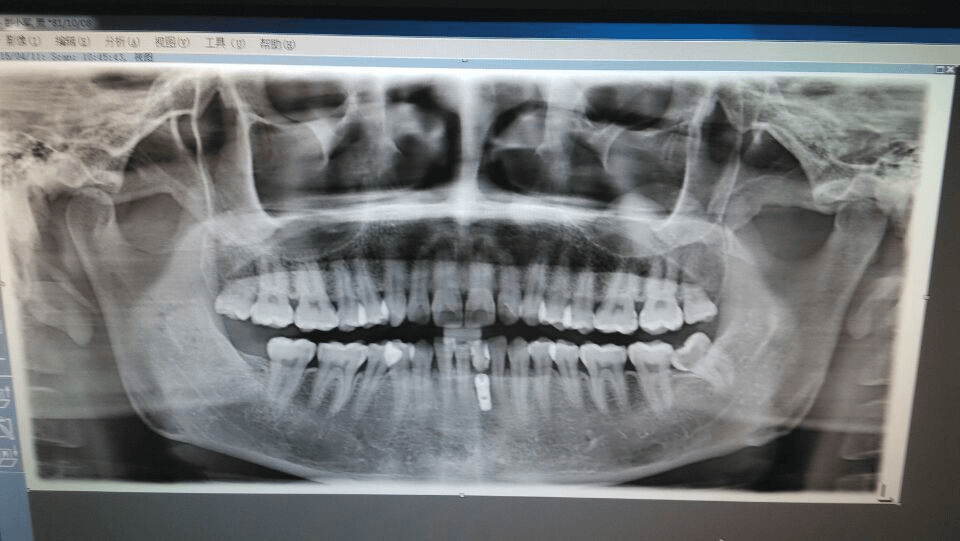

随后,他又去过多家医院,但都没有找到合适的治疗方法。直到2014年,彭先生第一次通过他的主治医生黄医生了解到了种植牙修复。无需拔牙,也不用戴烤瓷牙,完全满足了他的修复要求。他兴高采烈得到了医院咨询,经过专家会诊后,却只得到了“缺牙患处直径只有3.5毫米,不符合种植条件”的答复。几乎放弃的彭先生,最终在黄医生“有韩国医生”的推荐下,抱着死马当活马医的心态来到了康源口腔。

彭先生回忆说:“没想到当时片子拍完,宋医生居然说可以种,还成了直播案例。我想治疗肯定很有把握,否则也不会直播。”2015年4月11日上午10时4分,彭先生在《杭城首个种植牙现场直播全民公开课》活动现场300多名老少市民的欢送下进入手术室。

手术从麻醉、切开牙龈,到植入种植体,最后缝合,带上临时牙冠,仅用了19分钟。在现场观众的惊叹声中,彭先生与康源口腔的韩国医生宋大根院长一起回到了直播现场,不仅行动自如、表情轻松,还清晰得回答了主持人和观众朋友的诸多疑问。而这困扰了彭先生11年的缺牙难题,没想到竟19分钟就解决了。